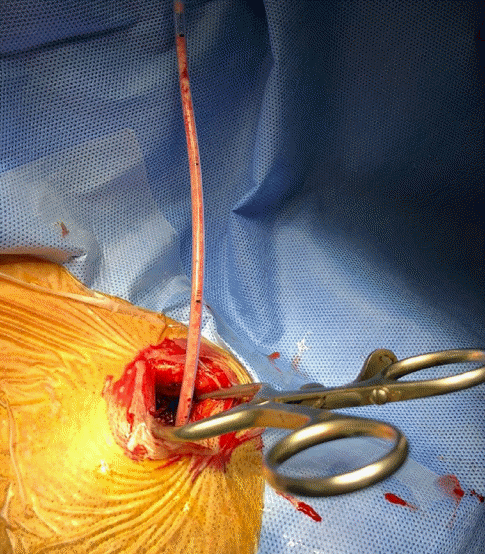

Fig. 3.

Intraoperative photograph shows a 3-cm skin incision and insertion of the catheter through the burr hole. The aspirated infarction tissue is observed in the inserted catheter.